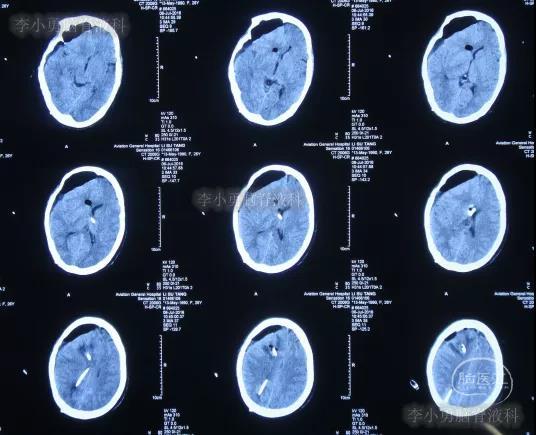

入院治疗62天即2016年7月6日,头颅CT脑室缩小,但仍有脑外积水(图-23)。

图-23:2016年7月6日头颅CT

入院治疗63天即2016年7月7日,拔除一根脑室外引流管(图-24)。

图-24:2016年7月7日头颅CT

入院治疗116天即2016年8月29日,脑积水大有改善(图-25)。

图-25:2016年8月29日头颅CT